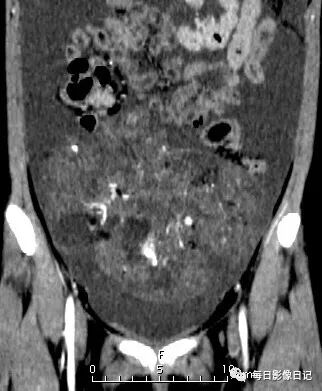

【影像所见】:

平扫腹部囊实性混杂密度肿块,以实性为主呈片絮状,可见散在不规则钙化(红箭示)及脂肪密度(白箭示),可见多个小囊,囊壁厚薄不一;

动脉期肿块实性部分及囊壁呈轻度不均匀强化;

静脉期及延迟期实性部分及囊壁进一步强化,可见包膜(蓝箭示指);

可见其内增粗穿行肿瘤血管(红箭示)及小囊(粗白箭示),另见腹腔大量积液。